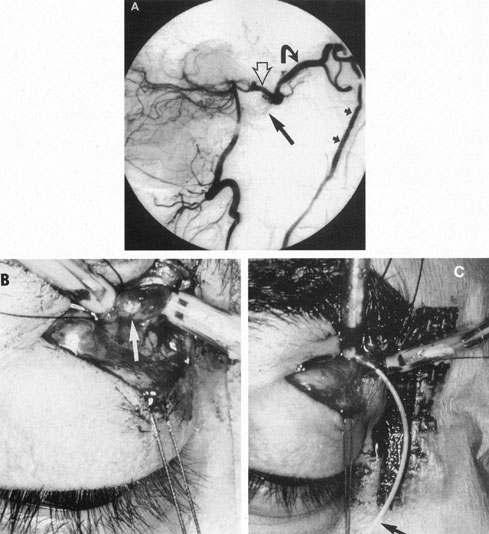

The therapy for AVMs has been reviewed elsewhere.91–93 The preferred treatment remains complete surgical excision of the malformation. However, significant advances in endovascular and radiosurgical techniques have resulted in a marked increase in the use of multimodal, staged approaches to AVM treatment. A variety of intravascular techniques use embolization91 with materials such as particles of polyvinyl alcohol (PVA), platinum coils, and injection of liquid N-butyl-cyanoacrylate (NBCA) adhesive (Fig. 11). Complications of intravascular embolotherapy include vessel perforation by the catheter, migration of embolic materials, and infarction and hemorrhage of normal brain.

Fig. 11. Embolization of middle cerebral vessels that supply occipital lobe arteriovenous malformation (AVM). The patient had a subarachnoid and intraparenchymal hemorrhage that produced a left homonymous field defect. A: Right carotid arteriogram demonstrates contribution via posterior communicating artery to a right occipital lobe AVM. B: Vertebral injection. The arrow points to the enlarged right posterior cerebral artery that is a major feeder of the AVM. C: Right carotid arteriogram during glue embolization procedure. The arrow points to a catheter as it traverses the segment seen in (B). The catheter was advanced via the internal carotid artery but is positioned far posteriorly. D: Upper branches to the AVM now are occluded, with residual low-flow vascularization via the middle cerebral artery. E: Skull film showing radiopaque glue within the AVM and blood vessels previously supplying it. The patient had a persistent visual field defect but greatly reduced headache and no persistence of subjective bruit. (Courtesy of Dr. Joseph Horton.)